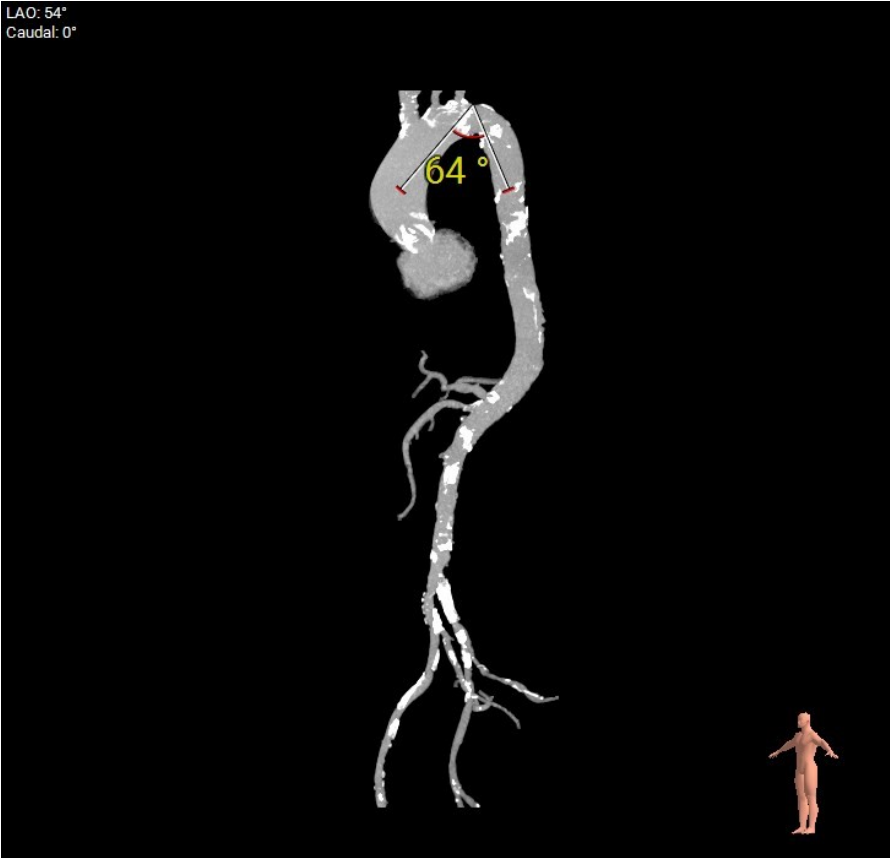

CT评估-外周测量:双侧入路偏细,左侧入路小于5.0mm,右侧髂外段入路最小约5.3mm,见三段长条钙化,考虑输送系统通过难度极大;锐角弓约64°,弓部到髂股动脉钙化较多,股动脉分叉皆位于股骨头以下

瓣膜选型:Evolut PRO+26mm